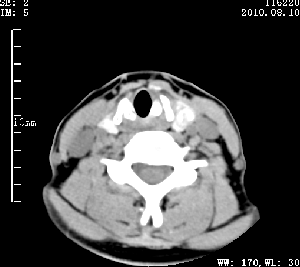

标题: CT28317:病人近几天无意间发现颈部肿块。 [打印本页]

标题: CT28317:病人近几天无意间发现颈部肿块。

甲状腺左叶局限性结节性甲状腺肿可能。建议增强扫描。

病变边界清楚,周围间隙清晰,甲状腺左叶(甲状旁腺?)肿大,右叶甲状腺腺瘤。

病变边界清楚,周围间隙清晰,左叶甲状腺肿大,右叶甲状腺小腺瘤。